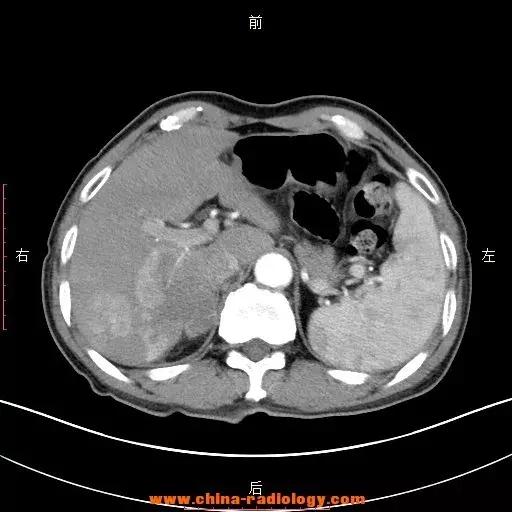

Fig 5 肝占位

考虑占位性病变,建议某某检查

占位性病变是医学影像诊断学中的专用名词,通常出现在X射线、B超、CT等检查结果中。

是指被检查的部位有一个“多出来的东西”,这个“多出来的东西”可使周围组织受压、移位。

占位性病变通常泛指肿瘤(包括良性的、恶性的)、寄生虫等,仅仅是个现象而不涉及疾病的病因。

占位性病变绝不等于是癌症。

临床工作中,如果征象典型,可靠性80%-90%以上,一般报告肺癌可能性大、肝癌可能性大等。若可靠性在60%-70%,表述为:考虑占位性病变,医生会要求患者提供更详细的病史,以及参考其他检查,进一步明确诊断。各系统占位性病变最终诊断依赖于病理检查(穿刺取样或直接切下来放在显微镜下观察)。